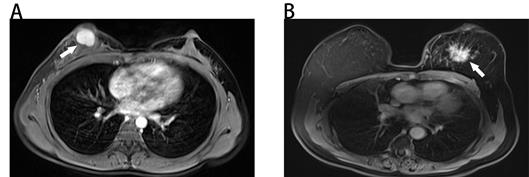

The results of univariate and multivariate logistic regression analyses were illustrated in Table 2. Based on the result of univariate logistic regression analysis, we found that age, tumor size, mass shape, mass margin, internal enhancement characteristics, and kinetic curve were significantly associated with malignancy. According to the result of multivariate logistic regression analysis, five variables were identified as independent predictors in our study, including age, tumor size, mass margin, internal enhancement characteristics and kinetic curve. Typical MRI findings of benign and malignant breast masses were illustrated in Fig. 1.

Figure 1

Benign and malignant breast masses on MRI. (A) Benign-looking breast mass of 17×12mm (arrow), oval, circumscribed margin and homogeneous enhancement in a 40-year-old woman. Pathological diagnosis: fibroadenoma. (B) Malignant-looking breast mass of 36×32mm (arrow), irregular, non-circumscribed margin and heterogeneous enhancement in a 60-year-old woman. Pathological diagnosis: invasive ductal carcinoma.